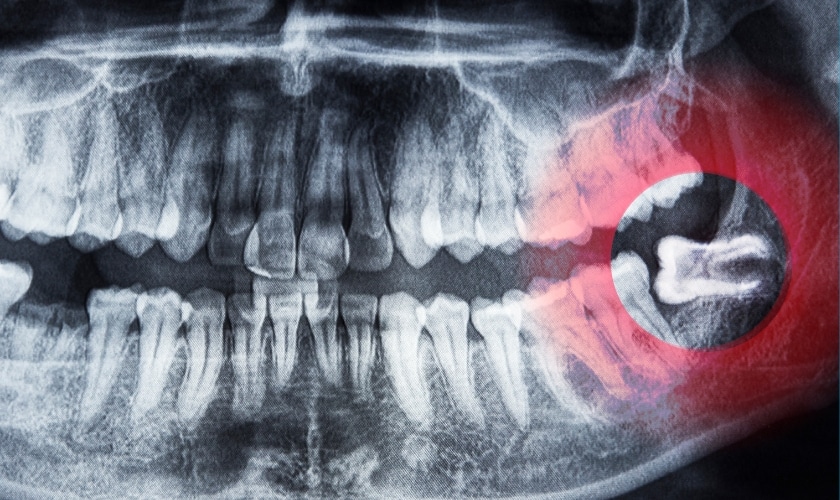

While some wisdom teeth erupt smoothly and cause no problems, others aren’t so lucky. They can become impacted, meaning they’re stuck under the gum or bone, leading to pain, infection, and other dental issues. In these cases, removal is often recommended.

1. Impaction: This is the big one. Up to 85% of wisdom teeth get stuck (impacted) under the gum or bone, causing pain, swelling, and infection. Imagine a crowded subway at rush hour, but with teeth!

4. Cyst city: Neglected wisdom teeth can form cysts, fluid-filled sacs around the root that can damage the jawbone and nerves. Not fun!